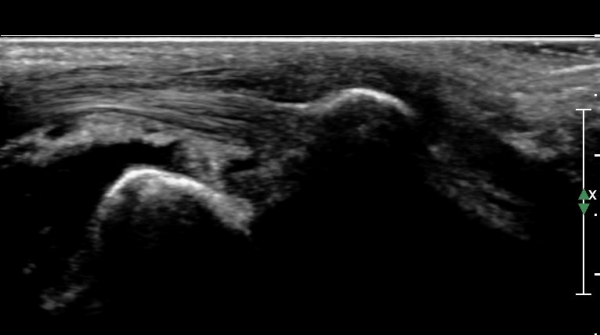

¹ß¸ñ ¿ÜÃø Ⱦ´Ü¸é(ºñ°ñ°Ç Ⱦ´Ü¸é)°Ë»ç¿¡¼­ ºñ°ñ°Ç ½ÉÃþÀÇ ´Ù·®ÀÇ ¼ö¾×Àú·ù°¡ °üÂûµÈ´Ù

(»çÁø 5, 6).